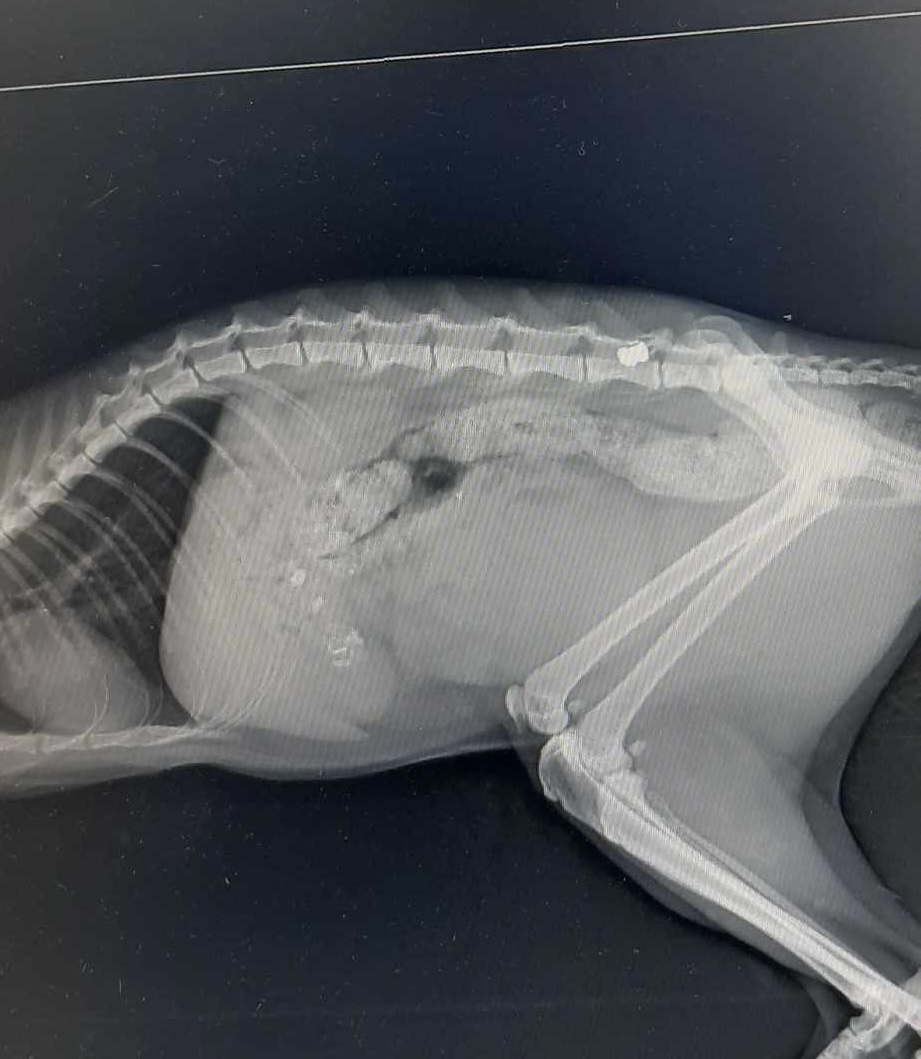

Η επίσκεψή της κατοίκου, όμως, στον κτηνίατρο αποκάλυψε πως το ζώο είχε πυροβοληθεί, προκαλώντας ακόμα μεγαλύτερη ανησυχία για το γεγονός ότι κάποιος φαίνεται να χρησιμοποιεί όπλο.